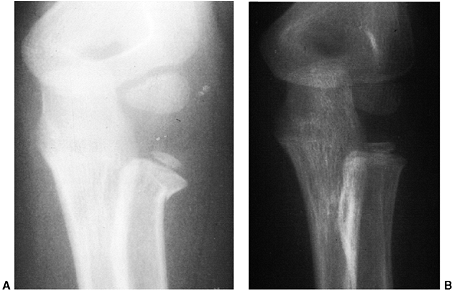

nerve function. Neurovascular problems are frequent, and fracture

management may be altered if neurovascular compromise is present. In

the absence of neurovascular compromise, displaced fractures can be

splinted and managed safely in a delayed manner as long as the child is

closely monitored (132,133). Primary CRPP is the preferred treatment for type III injuries (134) (Fig. 33.18).

Displaced supracondylar fractures treated by closed reduction and

casting have a higher incidence of residual deformity than those

treated with reduction and pinning (134). Closed reduction and casting also has a higher risk of Volkmann ischemic contracture than treatment with early pinning (134).

experience has demonstrated that two or three laterally placed pins are sufficient for stabilization (137).

The authors prefer laterally placed pins without a medial pin except in

unusual circumstances. When a medial pin is used, one should be aware

that extreme elbow flexion could result in ulnar nerve subluxation from

its groove and increase the risk of damage during pinning. When

possible, it is advisable to place the lateral pin first to provide

provisional stability so that the medial pin can be inserted with the

elbow in less than full flexion, placing the ulnar nerve farther

posterior. It is also advisable to make a small incision over the

medial epicondyle and dissect with a hemostat, so that the medial pin

can be placed directly on the bone. Anatomic alignment is preferred,

but this may be difficult to achieve in some cases. When the quality of

reduction is in doubt, comparison radiographs of the opposite elbow can

be obtained intraoperatively. The Baumann angle should be within 5 to 8

degrees of the angle on the contralateral side. As long as fixation is

secure, it is the author’s opinion that one may accept up to one-third

translation of the distal fragment, 30 degrees of malrotation, and 20

degrees of extension after pinning (capitellum anterior to the anterior

humeral line). Initial immobilization should be in a nonconstrictive

splint or cast with the elbow in less than 90 degrees of flexion. The

authors prefer a cast that has been bivalved and spread with the elbow

in approximately 70 degrees of flexion. Oral analgesics are usually

sufficient for pain relief. The need for intravenous narcotics may

indicate ischemia. Immobilization is continued for 3 to 4 weeks, at

which time the pins are removed and active range of motion is initiated.

![]() |

|

Figure 33.18 Type III supracondylar humerus fracture. A: This type III fracture demonstrates lateral displacement. B:

The lateral projection also shows flexion of the distal fragment. The treatment of this less common position is the same as that for extension fractures. The posterior periosteum is torn, and hyperflexion of the elbow will excessively forward-flex the distal fragment. The elbow is best pinned at slightly less than 90 degrees of flexion, because it is technically difficult to pin the elbow in extension. C and D: Anteroposterior and lateral postreduction and pinning films. |

reduction through a medial approach, adding a lateral incision, if

necessary. An anterior surgical interval can also be used, and is

recommended if the neurovascular structures need to be exposed. The

posterior approach should

be

used cautiously because it disrupts any remaining intact soft tissue

and may disrupt the primary vascular supply to the distal humeral

fragment (122,123).

Complete vascular disruption is uncommon, because the thick local

muscle envelope protects the artery. Vascular evaluation after

reduction requires differentiation of the pulseless extremity that is

pink and viable from one that is cold and pale with vascular

insufficiency. The child who has a well-perfused hand but an absent

radial pulse after satisfactory closed reduction does not necessarily

require routine exploration of the brachial artery (129,138,140,141).

The pulse usually returns within 48 hours. Likewise, the absence of a